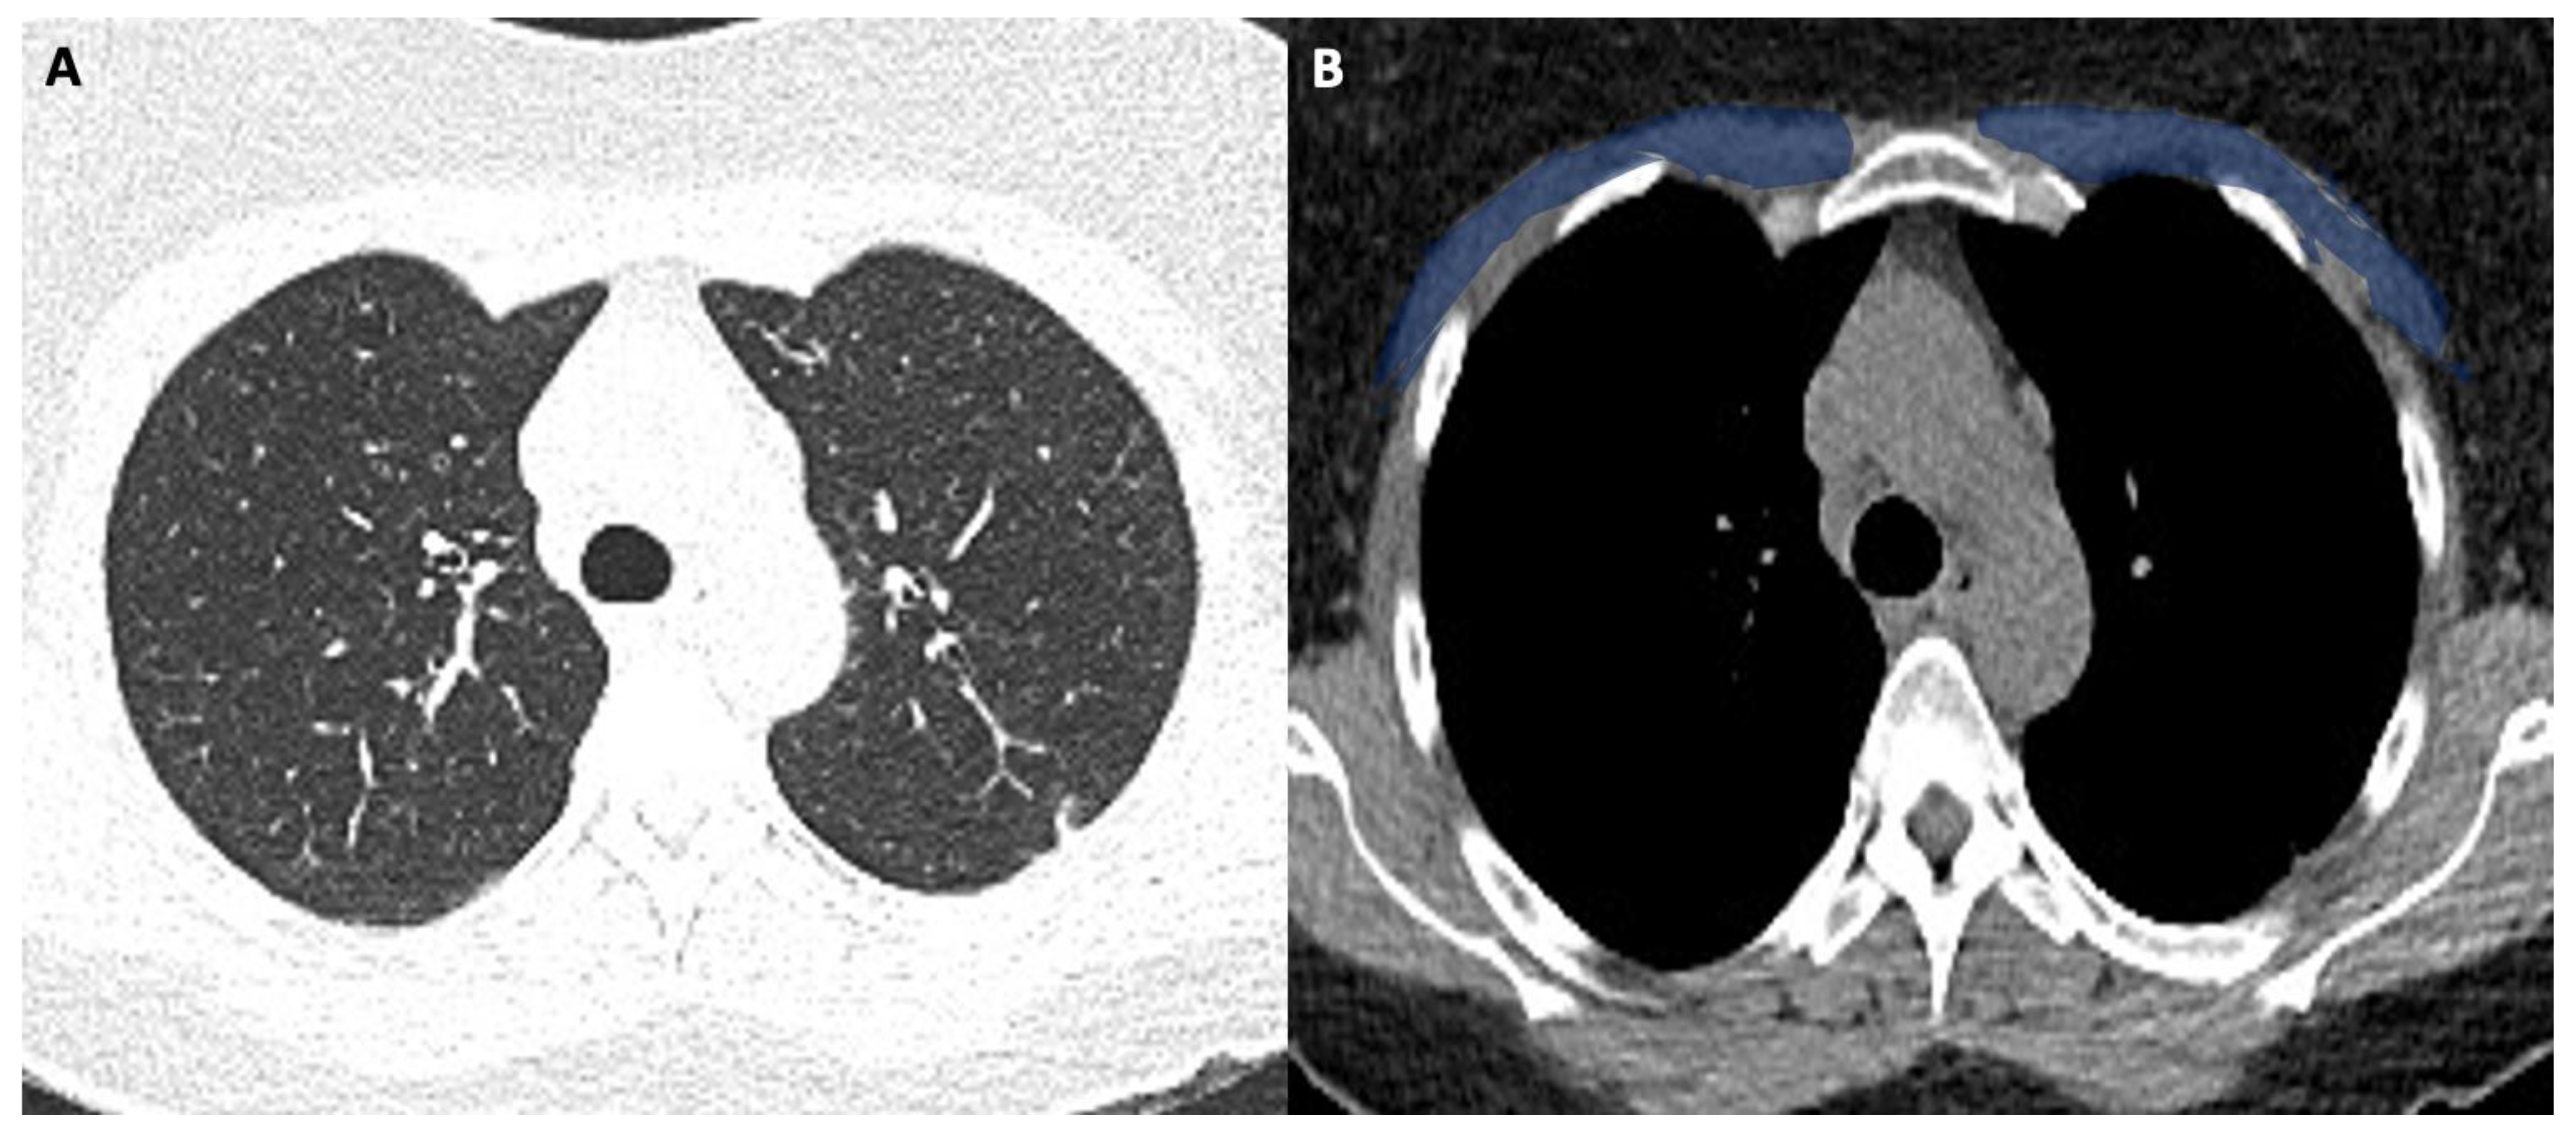

Figure 1 shows the modality of PMD and PMA evaluation. Figure 2 and Figure 3 show the examples of two patients enrolled in the study.

Figure 3A shows the CT image with lung window (pneumonia severity index score: 8). Figure 3B shows the corresponding level in the mediastinal window with a low pectoral muscle area (blue area). The patient had a long ICU stay, and he had extubation failure.

Figure 3. (A,B). 63-year-old male with COVID-19.